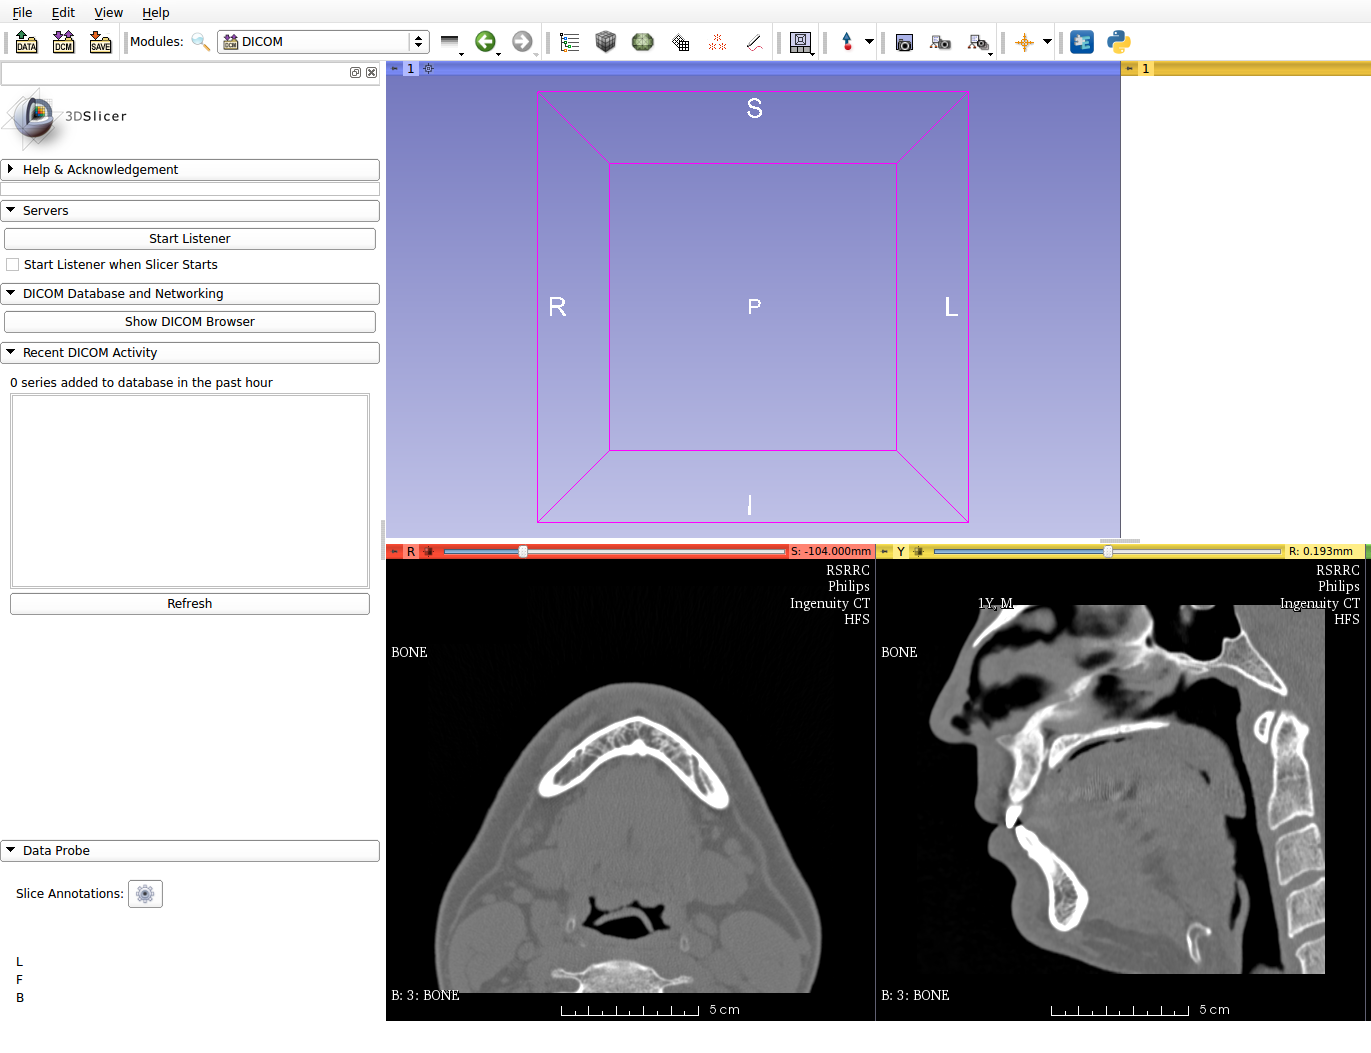

3D slicer намного более функциональный пакет чем InVesalius. 3D slicer для ученых-медиков, как Blender для 3D графики. Функциональный, но надо потратить время на изучение. У меня нет столько свободного времени и желания углубляться в этот софт. Лучше я продолжу писать статьи про аспектно-ориентированное программирование, а эти программы оставлю студентам-медикам и ученым. Для меня стало неожиданностью что столько медицинских программ есть в open source!!!

Использовал Imagemagic для кадрирования растра и сбора гиф анимации из отдельных снимков, а также инструмент командной строки dcm2pnm из пакета dcmtk:OFFIS DICOM toolkit command line utilities

dcm2pnm для извлечения растровых данных из формата DICOM

convert -delay 100 -loop 0 *.pnm animate.gif